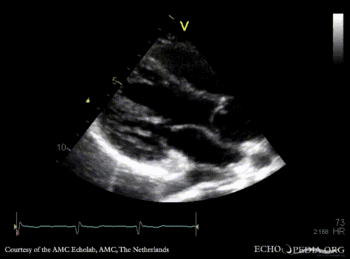

E00578.jpg

Pulsed-wave signal of pulmonary veins flow PSAX: dilated coronary sinus